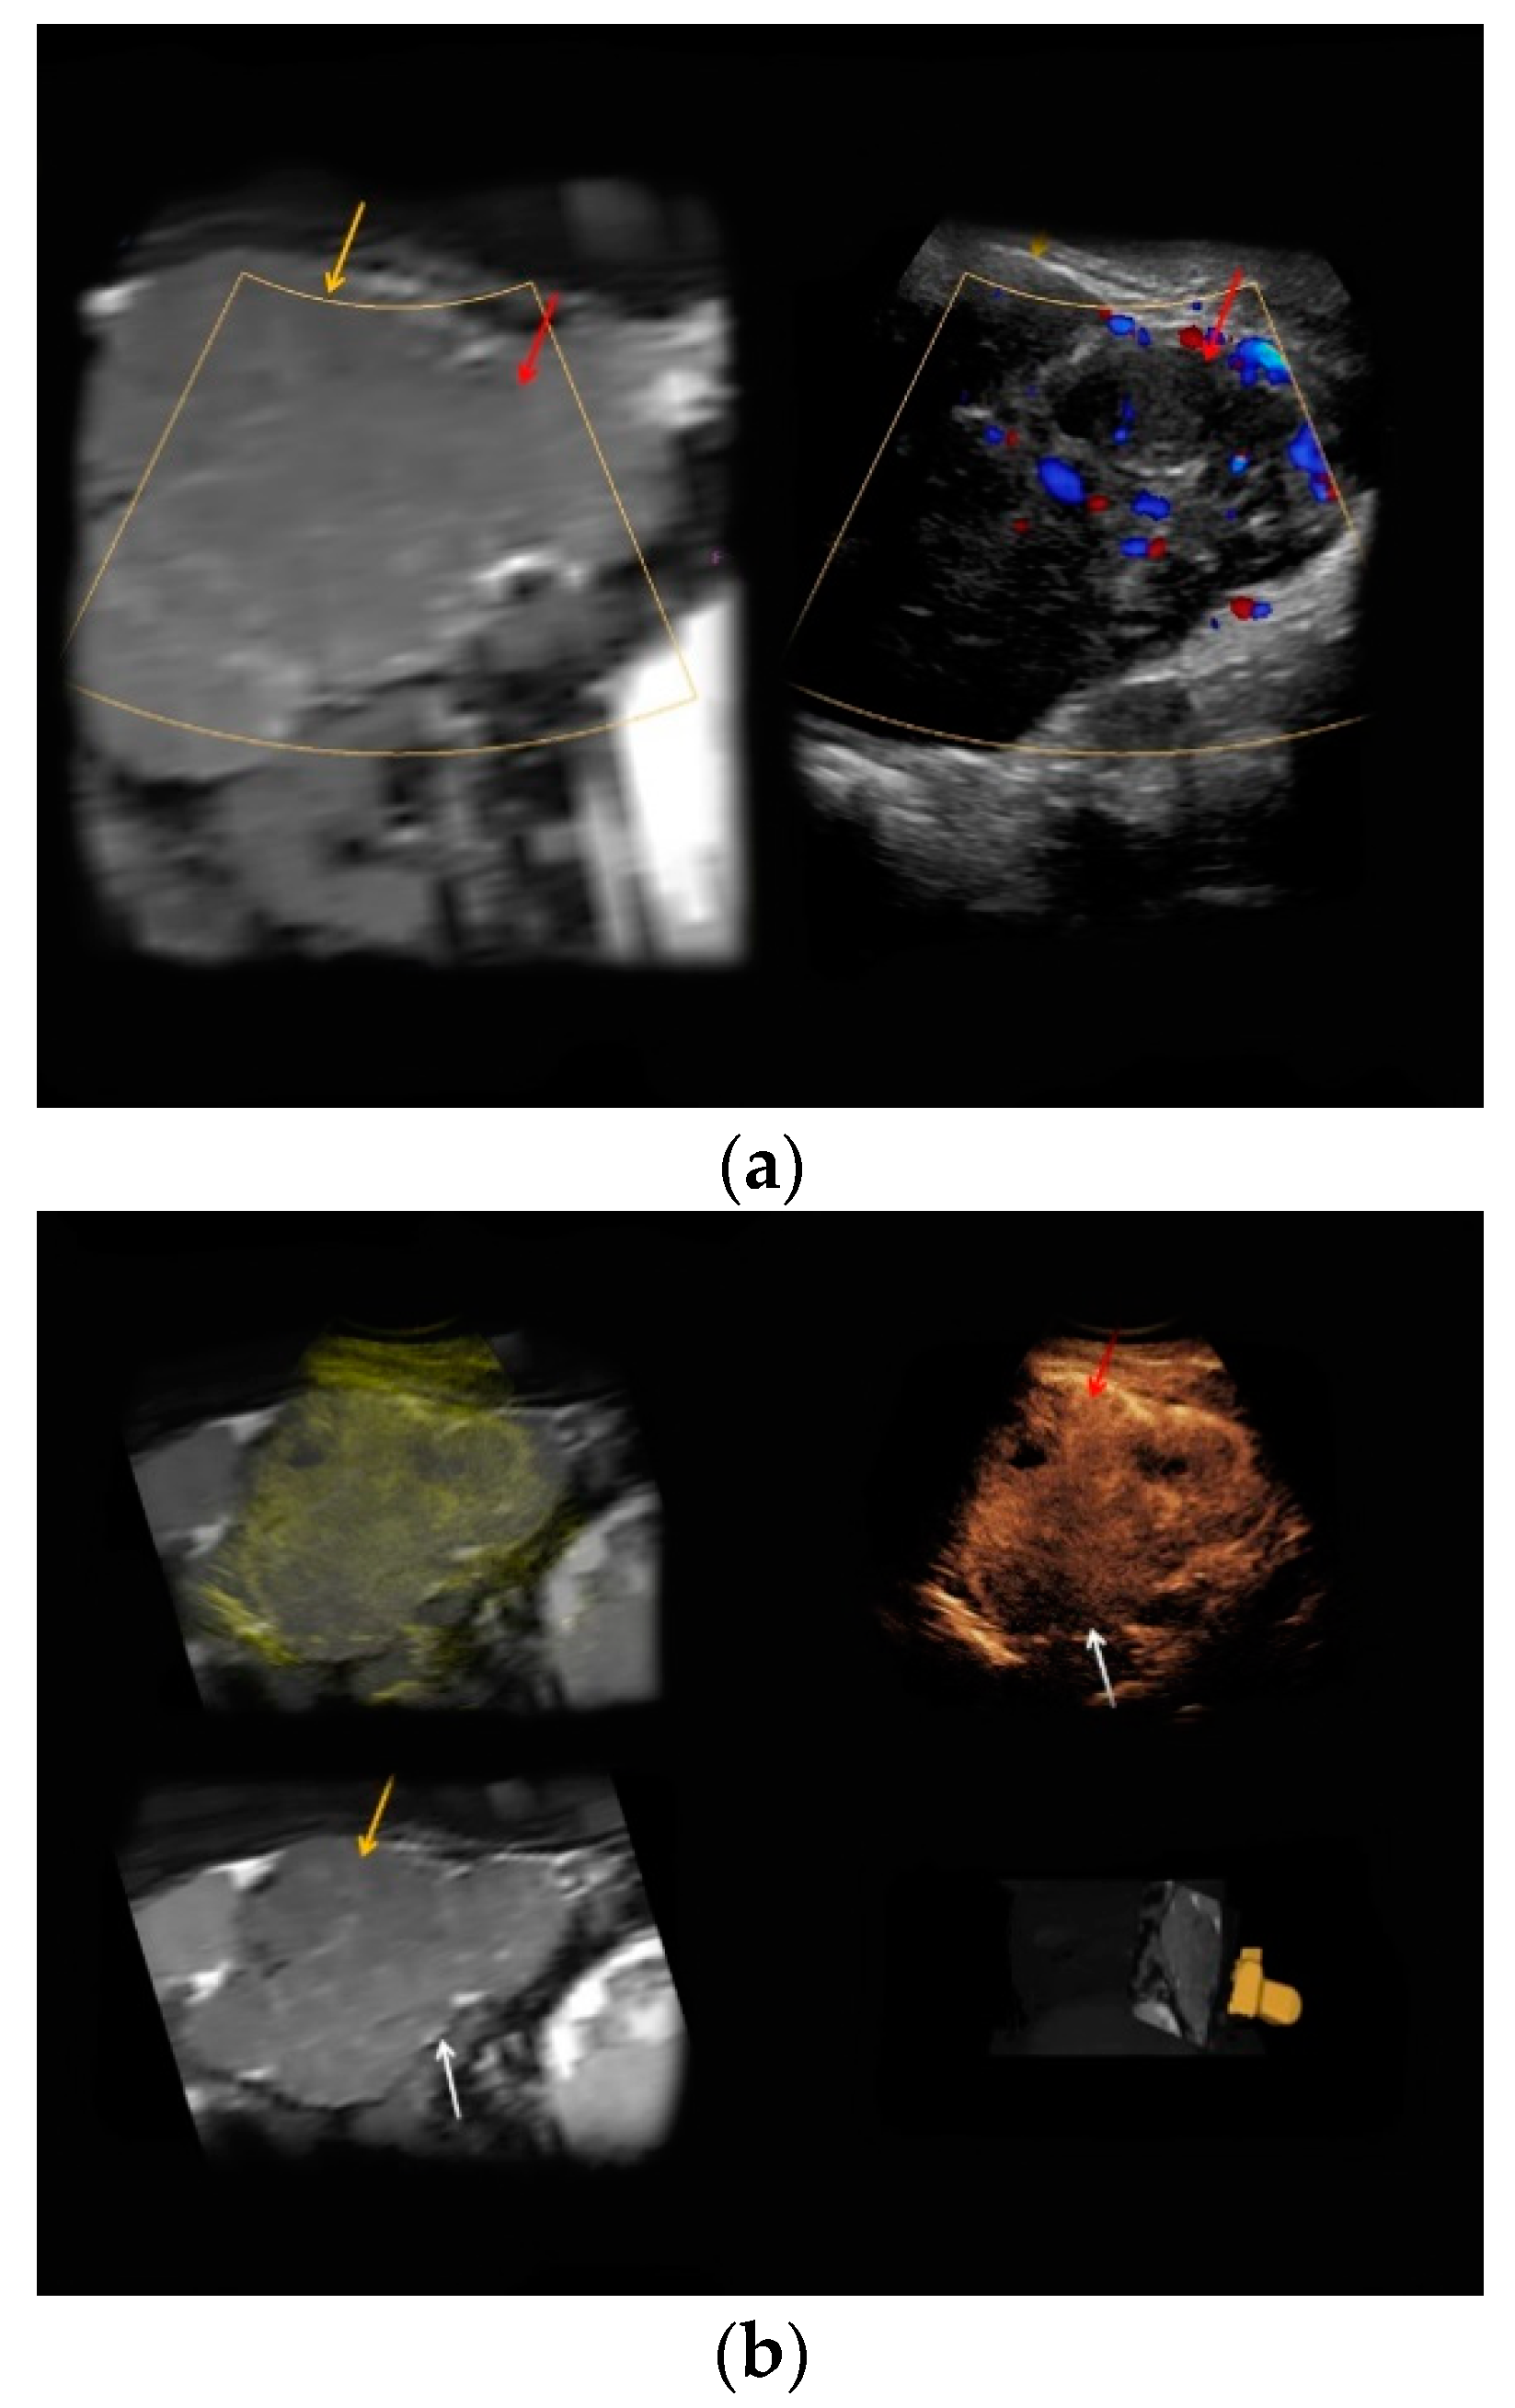

| #1 | 30 | 27 | Renal angiomyolipoma | B-mode: hypoechoic, 14 cm Doppler: no hypervascularization CEUS: rapid early contrast enhancement, slight late wash-out | T1-hypointense, T2-hypointense, restricted diffusion |